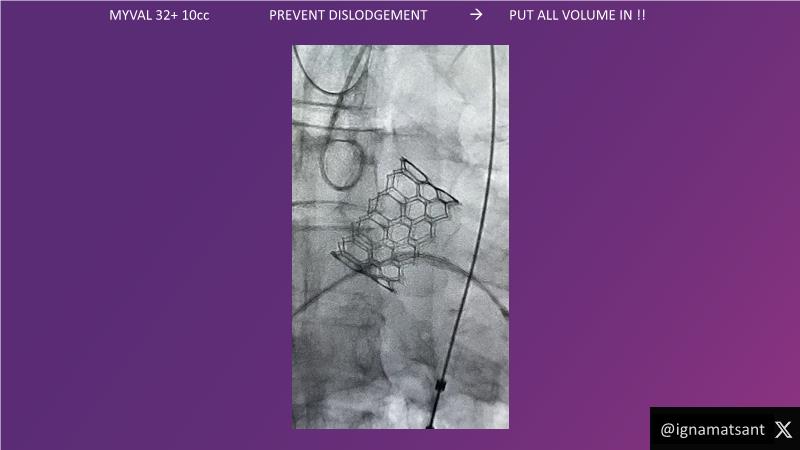

This session is a valuable resource for grasping innovative strategies in handling bifurcation and extended diffuse lesions through dedicated stenting solutions. Explore insights into the advanced Myval next-generation THV technology, unveiling its distinctive features, procedural advantages, and clinical outcomes across a diverse patient pool. Gain understanding into the CorAlign technique, ensuring accurate commissural and coronary alignment while maintaining coronary access. Additionally, delve into the techniques for precise sizing, positioning, and deploying of Myval THV.

- To understand the technique of precise sizing, positioning and deployment of Myval THV